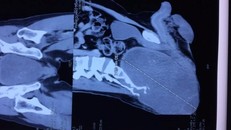

Phim chụp khối u của bệnh nhân. (Ảnh: PV/Vietnam+)

Cắt khối u khổng lồ vùng xương cùng cụt cho một bệnh nhân

Bệnh nhân tên Phạm Quang T. (40 tuổi, Hà Nội) với một khối u vùng mông to lên nhanh, khiến bệnh nhân không ngồi thẳng và nằm ngửa được từ một năm nay.